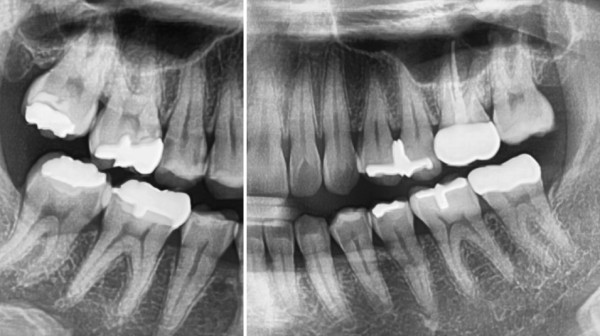

인접면 충치는 Proximal caires'라고 하고 '인접면 우식'이라고도 합니다.

말 그대로 치아와 치아가 인접한 사이에 생긴 충치를 의미한답니다.

이 충치가 무서운 이유는 바로 일반적인 환자분들이 스스로 찾을수가 없는 충치의 형태이고

치과의사 역시 육안검진을 했을때 발견하기 매우 힘든 충치이기 때문입니다.

위의 사진을 보시면 충치가 전혀 보이지 않죠?

이게 정말 무서운 점입니다.

이 환자분 역시 욱신거리는 통증이 있어서 저희 모란역치과 더서울치과를

찾아오시게 되었고 엑스레이로 촬영을 해본 결과 인접면에 사이충치가 확인된 것 입니다.